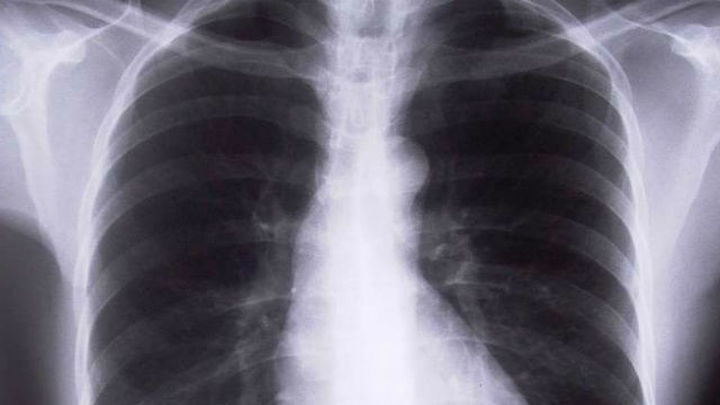

El carcinoma de pulmón, el tipo de cáncer que más muertes causa en el mundo, tiene los días contados

Un equipo de investigadores del Centro Nacional de Investigaciones Oncológicas ha logrado frenar el crecimiento de este tumor en ratones gracias a una nueva terapia.

El equipo de científicos del Centro Nacional de Investigaciones Oncológicas ha conseguido incluso curar en ratones, por primera vez, un tipo de cáncer de pulmón muy agresivo.

Y en concreto, han conseguido atacar y vencer al mecanismo que permite a las células canceríenas reproducirse sin límite.

La clave del estudio... bloquear una proteína que se encuentra en la telomerasa Es decir, las estructuras que protegen los extremos de los cromosomas.

El Centro Nacional de Investigaciones Oncológicas busca ahora socios en la industria farmacéutica que desarrolen estos fármacos para usarlos para combatir todos los tipos de cáncer.